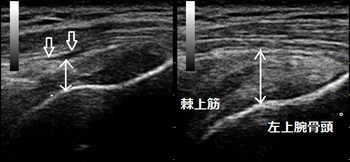

鶴ヶ島市 自営業男性 右肩関節の痛み 腱板(棘上筋)断裂

右肩患部 左正常側

超音波画像では患部のperibursal fatが落ち込んでいて断裂を示唆していました(画像⇩矢印)。また、筋肉の厚みも正常側と比較して減少していました(画像↕矢印)。